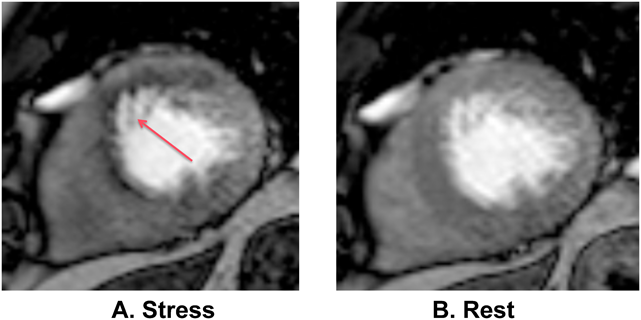

⑥Perfusion

SSFPシーケンスと造影剤を使用して心筋虚血評価を行うプロトコールである.通常はアデノシンによる薬物負荷での撮影(Stress)と安静時の撮影(Rest)を比較して,虚血の有無を判定する.虚血部位はStress下でdefectとして描出される(Fig. 12).視覚的定性評価,3Dワークステーションを用いた定量的診断両方の評価が可能である.心筋シンチと同等かそれ以上の精度でかつ,コストは約1/3で虚血の判定が可能とされる42).最近のメタアナリシスでは陰性的中率が98%であったとされる43).胸痛や冠動脈奇形・冠動脈移植術後評価などに用いられる.CHDや川崎病での報告もあり44–47),シンチグラフィと比較して被曝がなく,空間分解能が高い点で有利とされる48–51)

Pediatric Cardiology and Cardiac Surgery 32(4): 291-306 (2016)

Fig. 12 Short axis first pass perfusion magnetic resonance image